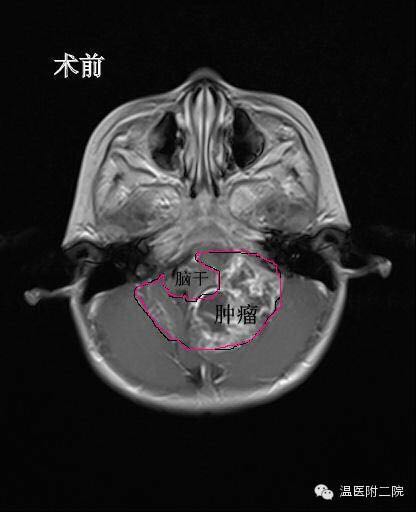

医生给俊俊做了脑部CT和核磁共振,检查的结果让该院儿童神经外科主任林坚大吃一惊:“后脑长了鹅蛋大小的一个肿瘤,直径有7cm*5cm*6.5cm。”这颗巨大的肿瘤紧紧包住了四分之三的脑干和好几条神经血管,手术风险极大。

据介绍,脑干维持个体生命,包括心跳、呼吸、消化、体温、睡眠等重要生理功能,是人体的生命中枢,稍有不慎就可能造成无法挽回的损失。但这还不是当务之急,迫在眉睫的是肿瘤堵塞了脑脊液的循环通路,造成了大量的脑积水,造成颅内高压已达临界。如不及时处置,不但肿瘤切除手术没法做,孩子随时都有停止呼吸甚至死亡的可能。“必须马上实施脑室外引流术!”经过脑室外引流术,俊俊的情况开始稳定下来,颅内高压被解除。

第二步要做的就是清除掉俊俊脑内的巨大肿瘤——把肿瘤和脆弱的脑干以及细小的神经血管精确地剥离,并且还要确保不能伤到脑干和血管。经过6个多小时的手术,俊俊脑内的“鹅蛋”被清理。在对肿瘤进行病理切片分析之后,确认俊俊的脑瘤是室管膜瘤三级,属于恶性肿瘤,需要进一步放化疗。